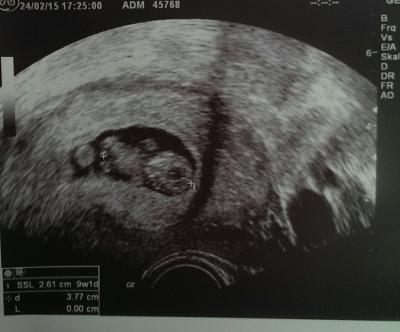

Bild zu Silopo - Schwanger - wer noch? Rund um die Schwangerschaft

Wunderschönes Bild hast du da